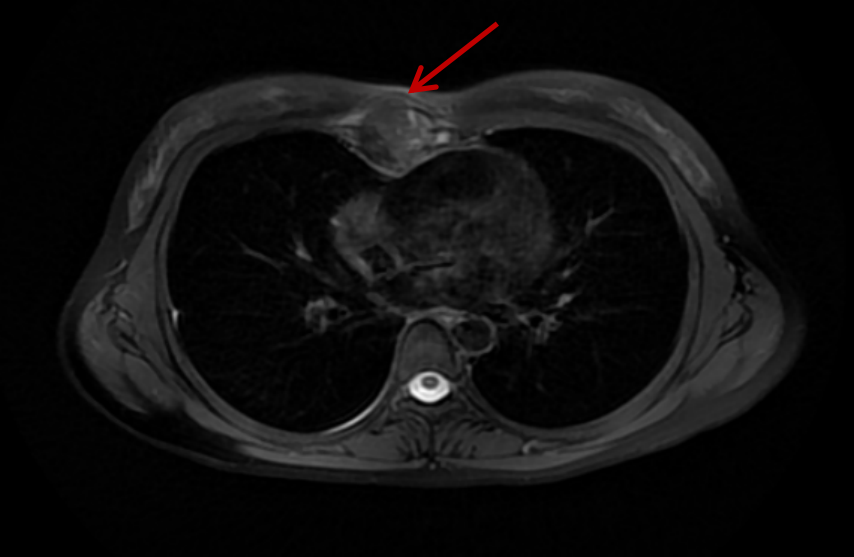

然而切除胸骨肿瘤牵涉着多方面的问题。在降低手术风险的同时,肿瘤发于胸骨已经生长到皮肤出现凸起,可见肿瘤之大,胸部MRI检查提示肿瘤大小达3.3×2.8cm,为确保彻底切除肿瘤,则需要切除足够的胸骨及周围结构,同时要在保障胸廓完整性及胸腔脏器不受影响的同时,维持正常的呼吸运动,这就大大增加了胸骨重建的难度;小林尚小的年龄,日后的工作、婚姻生活,则让胸外科的医师团队再三思量植入假体后,患者长久呼吸动度的韧性、耐久性,以及术中刀口的把握,如何让术后的皮肤尽可能美观,以尽可能地降低这位尚未婚育的90后患者的顾虑。

结合CT影像3D重建图像及以往该类手术的临床经验,陈东红组织全科进行多次病例讨论后,为手术准备充分的风险应对预案。手术按两大步骤有序执行——胸骨肿物切除,为了尽可能地清除肿瘤,术中将肿瘤附近的皮肤、皮下组织、距离肿瘤3cm以内的胸肌和肋软骨连同肿瘤整块切除,送检冰冻病理报告切缘阴性;经术中实际探查,肿瘤还没有侵及胸骨后筋膜及胸膜,经过精细的分离,保留了胸膜腔的密闭性,这为手术的第二步打下了好基础,在进行胸壁缺损修复时,采用了聚四氟乙烯(Poly tetra fluoroethylene,PTFE)包被骨水泥成形,对胸廓进行了重建,这一方法在保证胸廓完整性的基础上,满足了足够的胸廓移动度。